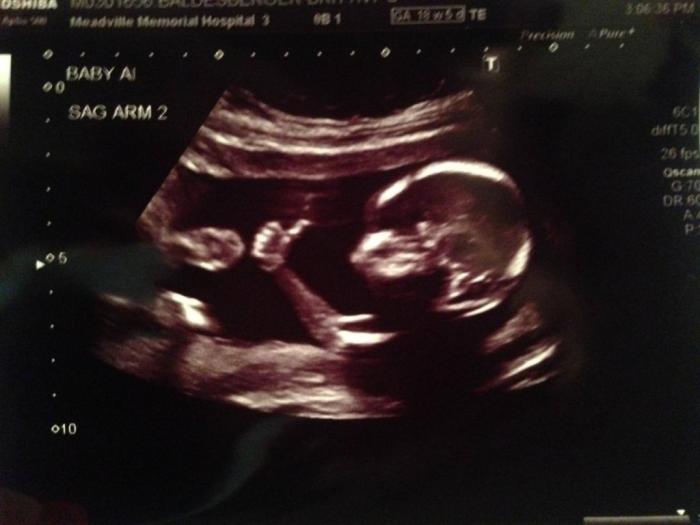

FOTO! A dat „LIKE” din pântecul mamei! Bebelușul născut pentru Facebook (și vești bune)

Un bebeluș a eliminat grijile părinților privind nașterea sa încă din uter! Micuțul le-a dat un semn incredibil!